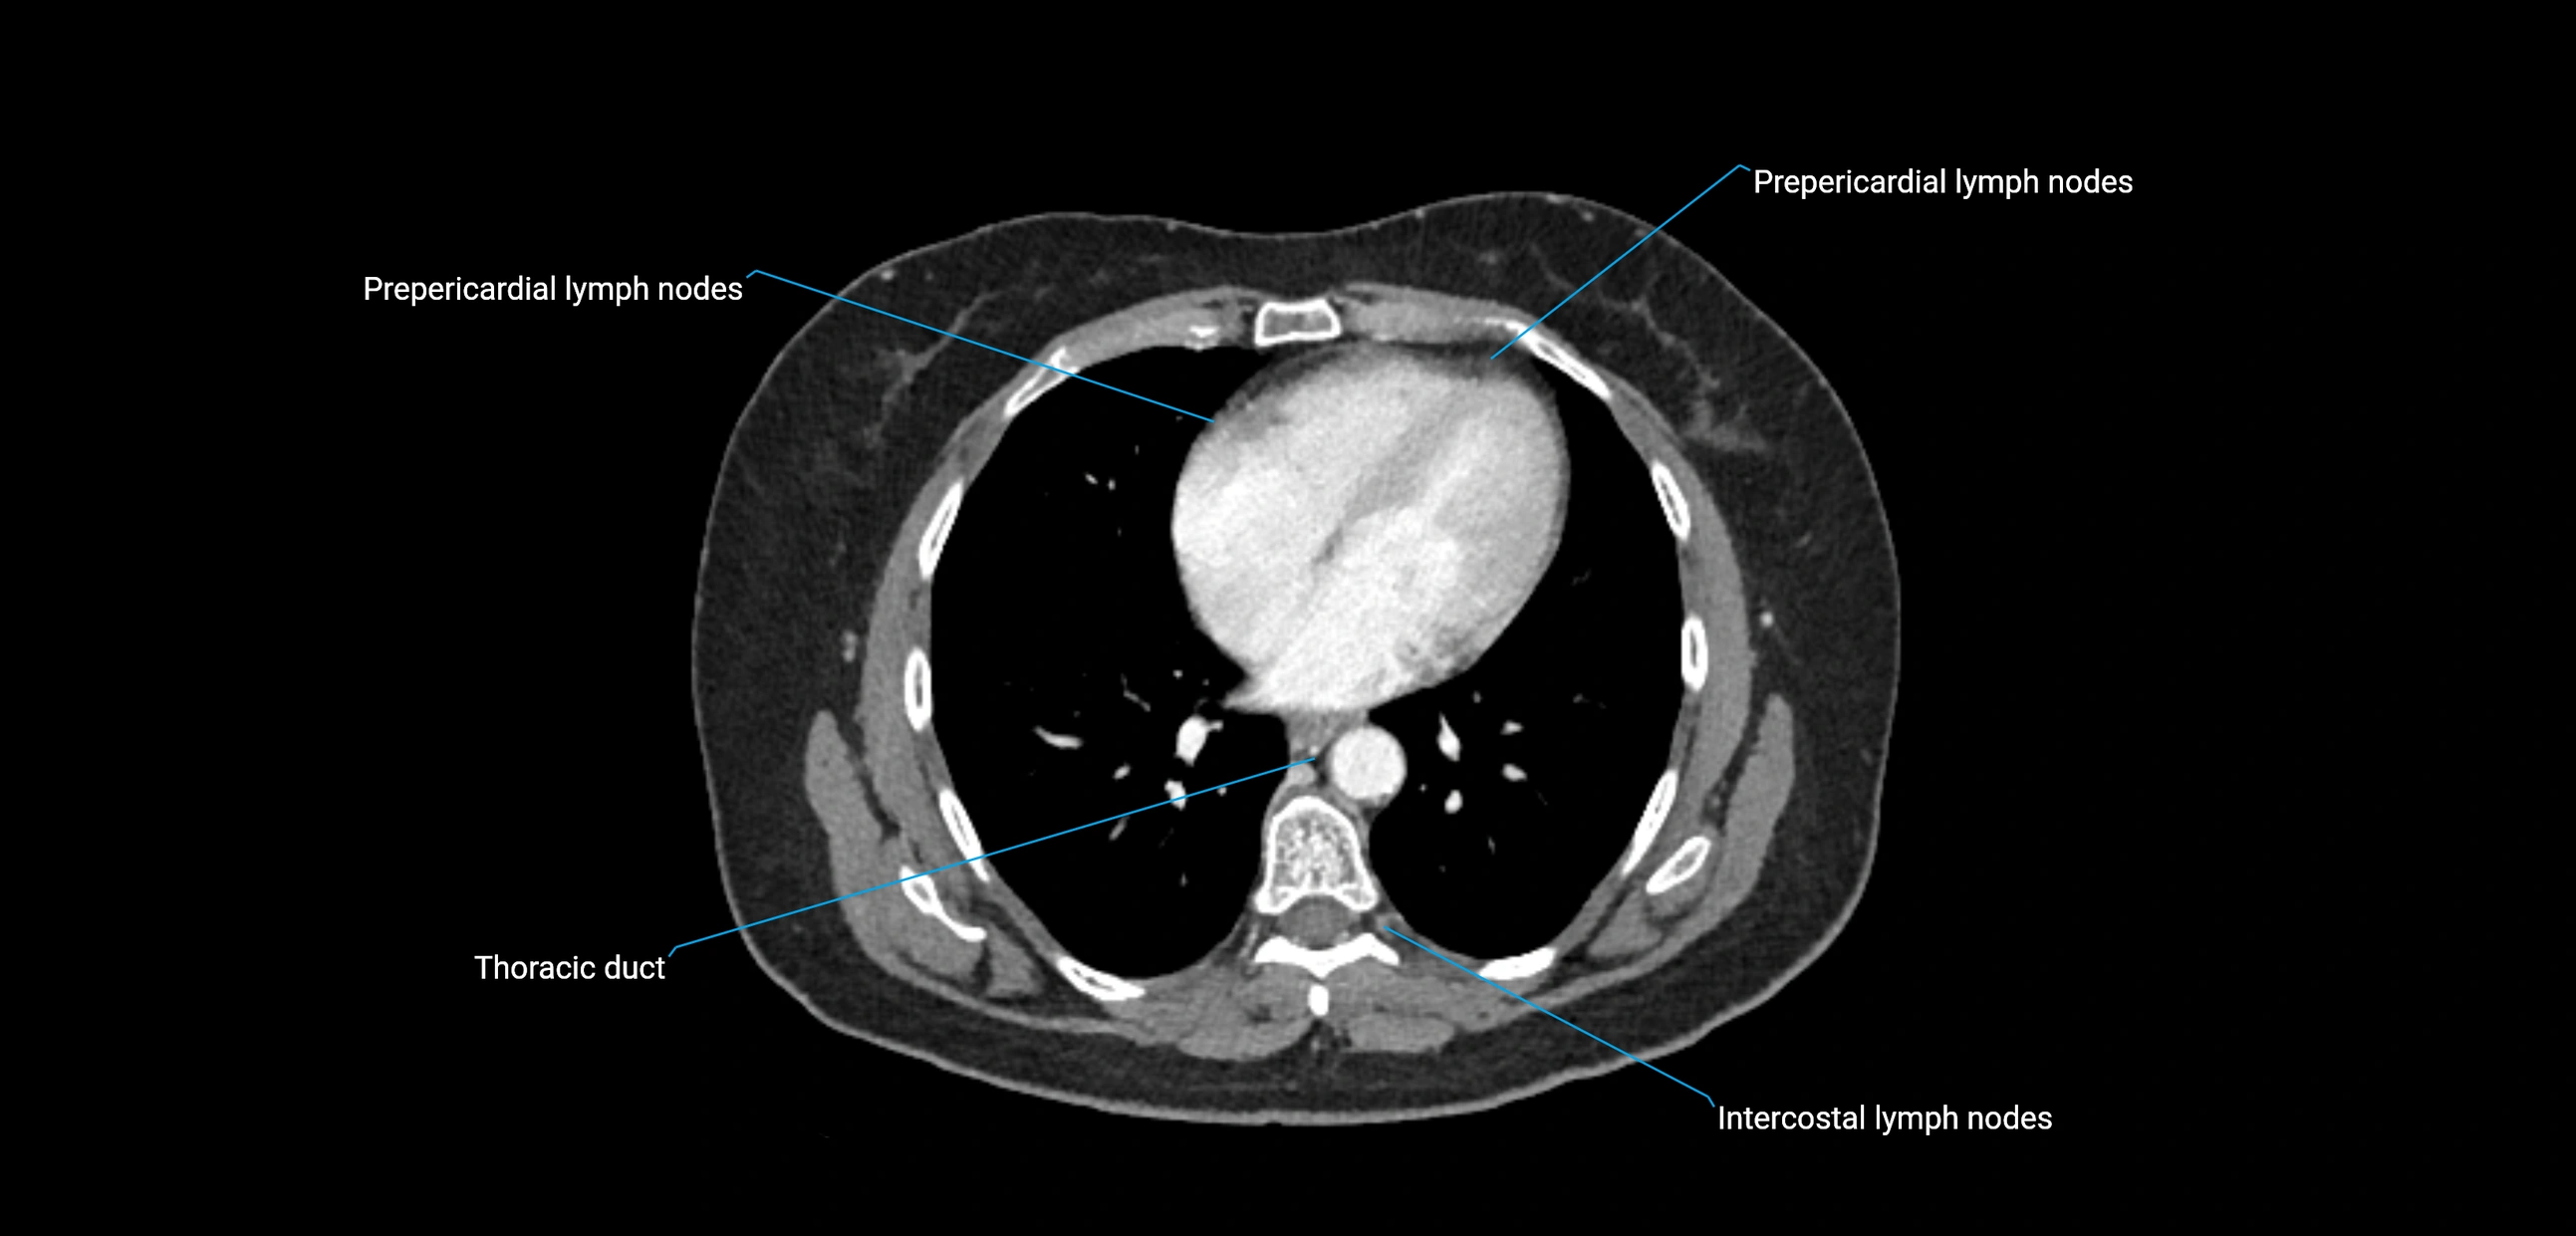

CT Appearance

CT Pre-Contrast:

• Nodes appear as soft-tissue density nodules adjacent to the aorta and IVC

• Calcification may be seen in chronic infections (e.g., tuberculosis)

CT Post-Contrast:

• Normal nodes enhance homogeneously

• Malignant nodes may show heterogeneous enhancement, central necrosis, or conglomerate formation

• Size >1 cm short axis is suspicious, though morphology and distribution are equally important